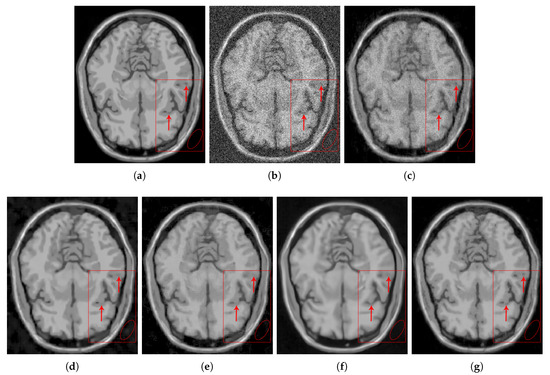

4.2.1. Synthetic Data

4.2.2. Real Data